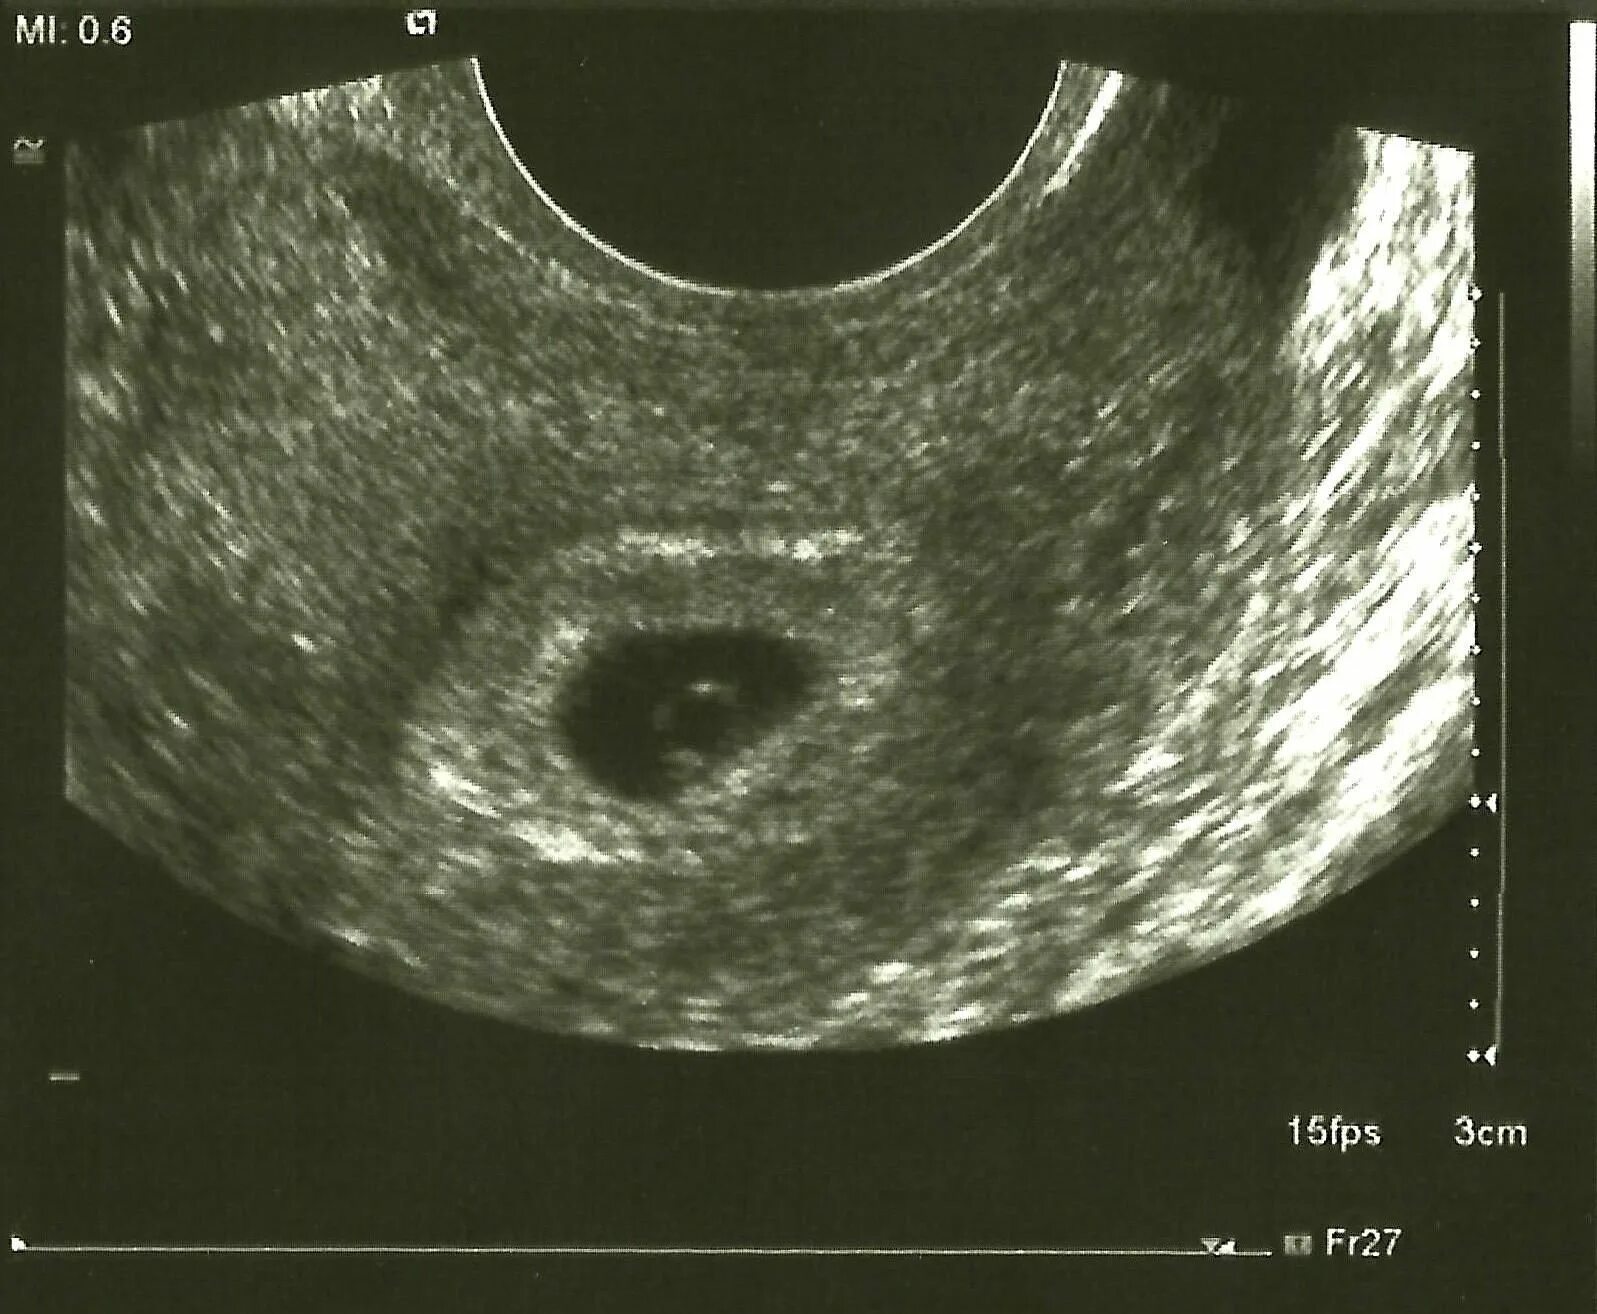

На 4 неделе беременности узи покажет беременность